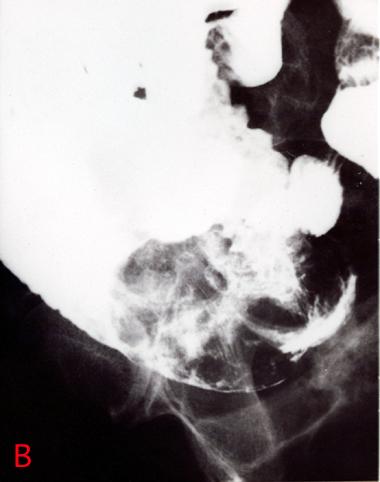

背景色の変更[ 画像ID:2374 ] 下血を主訴とした肺癌からの転移性小腸腫瘍(72才,男性)のX線像 経口法による小腸の造影X線像です。病変部を中心に示した写真で、回腸の内腔に約10cm大の大きな腫瘍が認められます。腫瘍の立ち上がりは急峻です。腫瘍は数個の結節状の隆起に分かれており、それらの間にバリウムが溜まって認められます。結節状に分葉した隆起の表面にも、淡いバリウムのたまりがみられ、腫瘤の表面にびらんを形成していることがわかります。 ■詳細データ